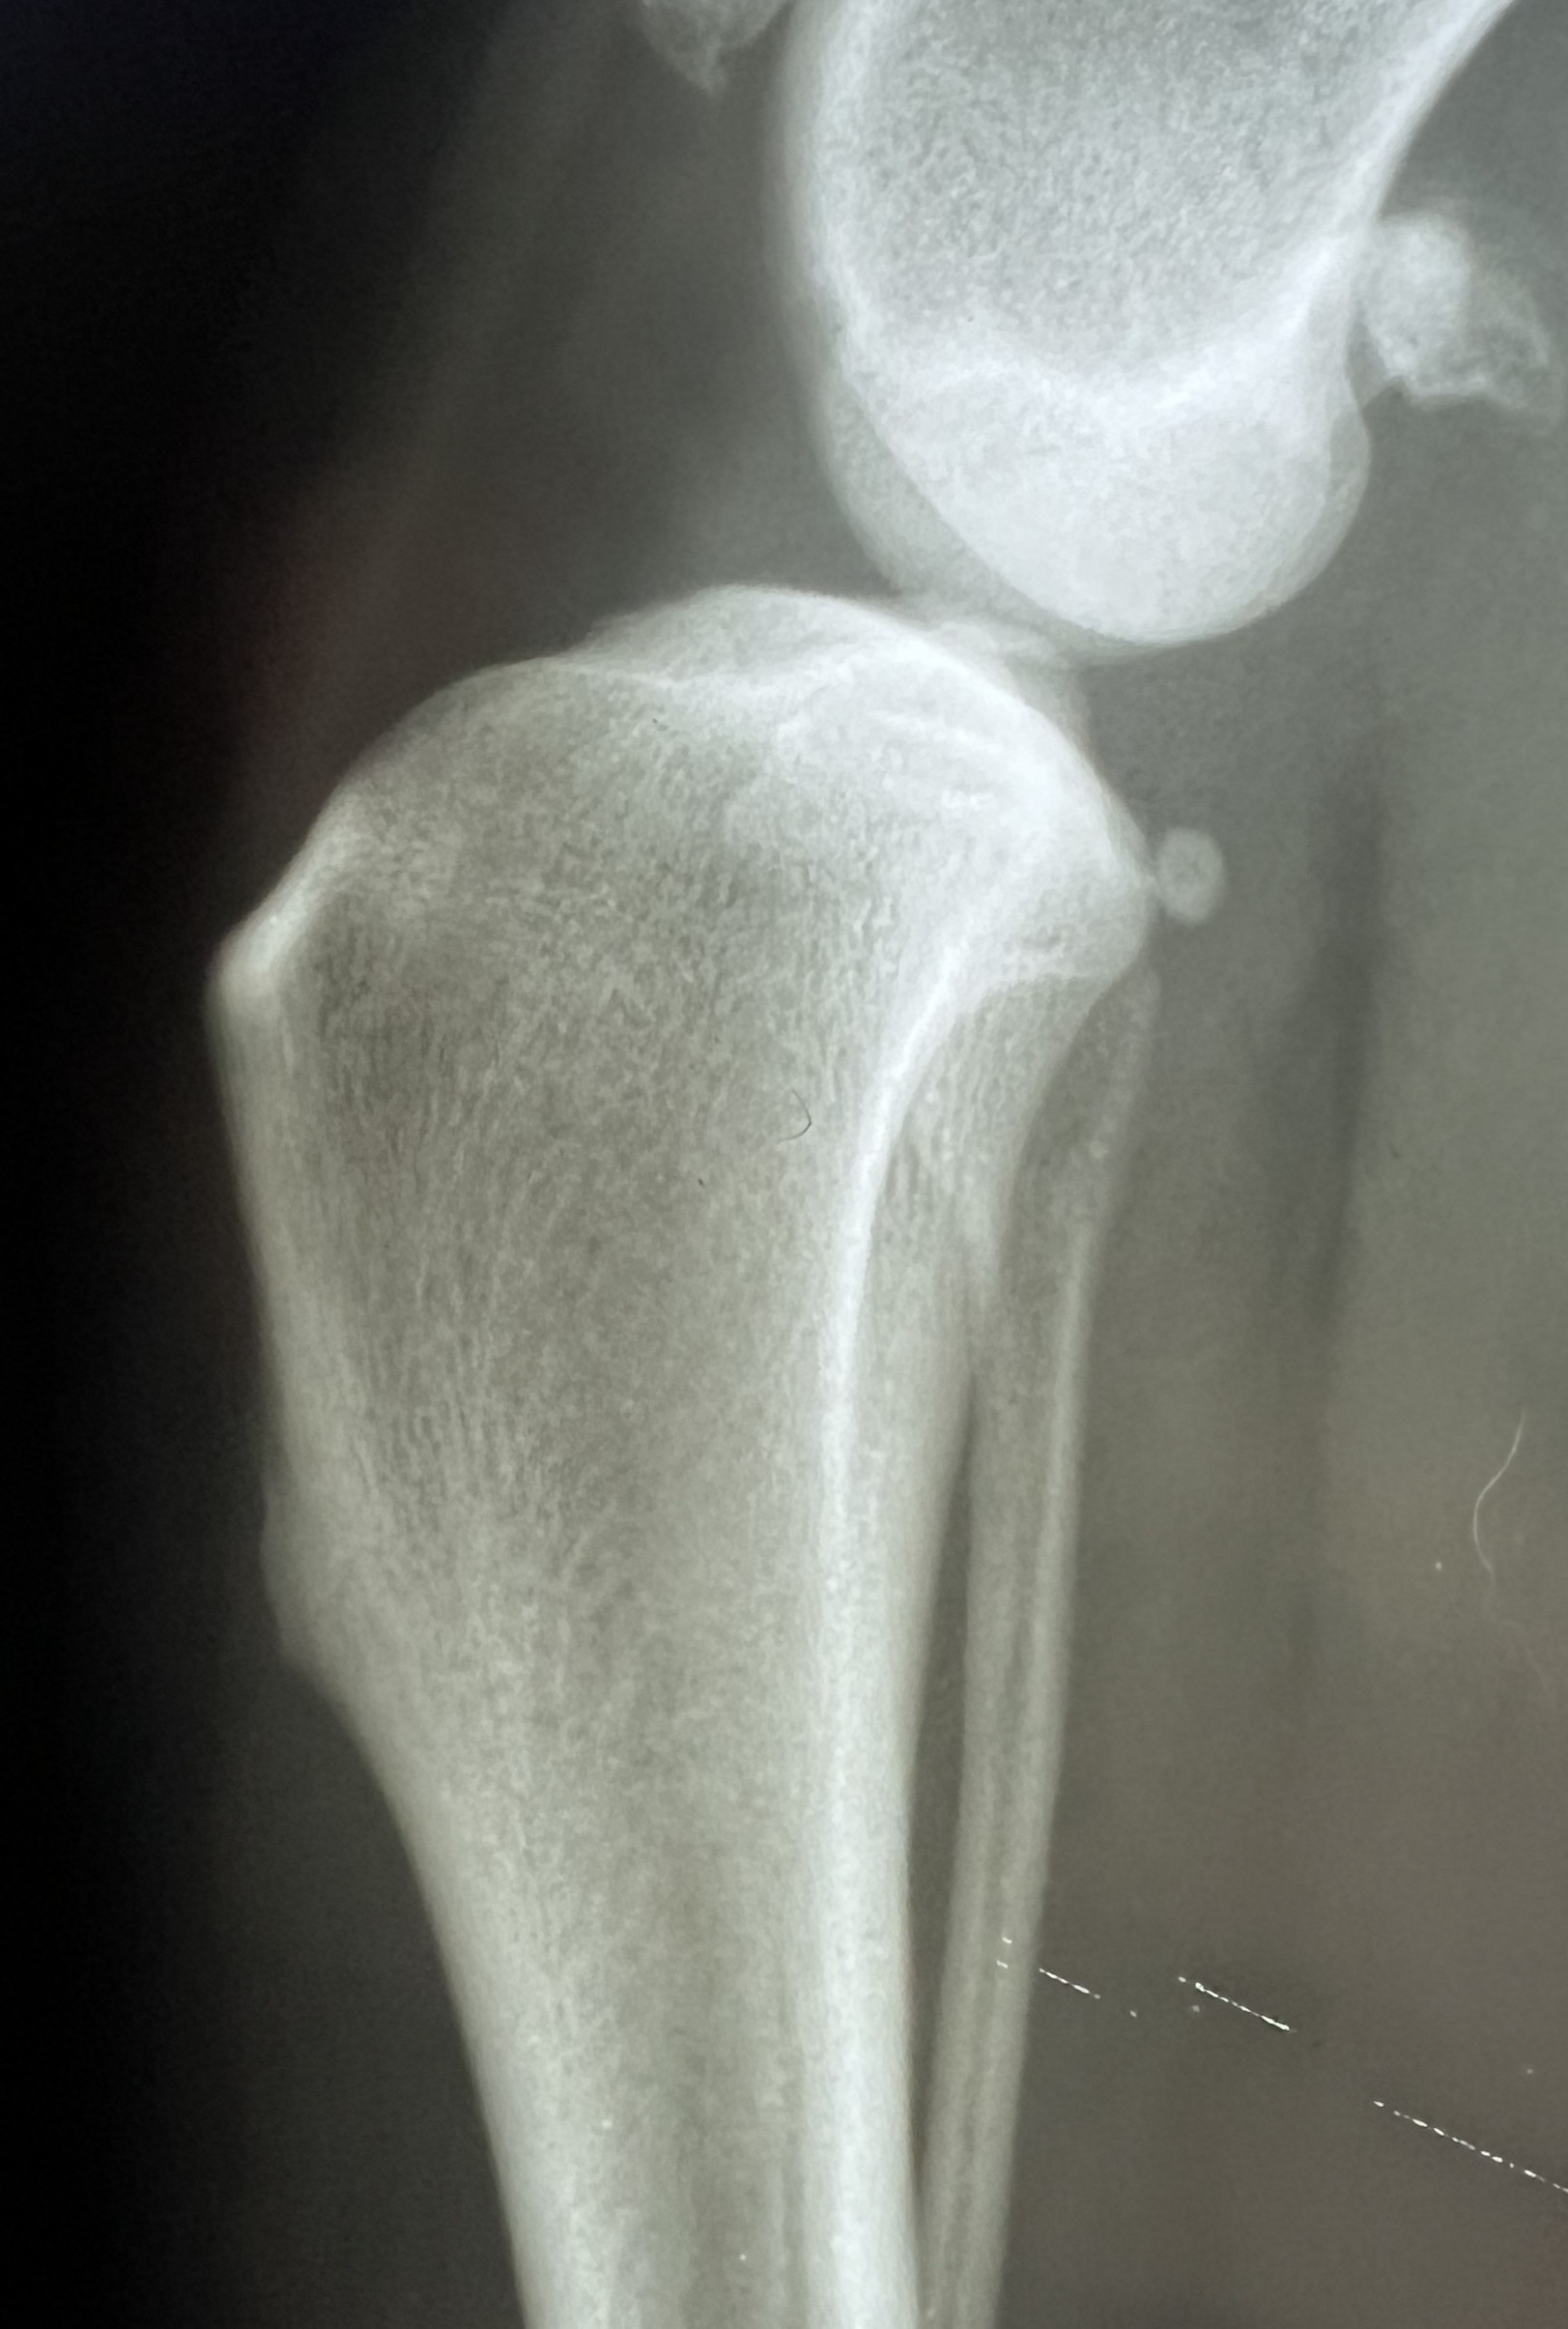

Diagnosis can be made from physical examination alone

but medical history and X-rays help to confirm the suspicion.

On exam, the veterinarian looks for abnormal forward movement of the tibia relative to the femur (known as cranial drawer or tibial thrust), which confirms damage to the ligament.

In partial tears, this motion may not be obvious, but pain on extension of the knee often helps identify the injury.